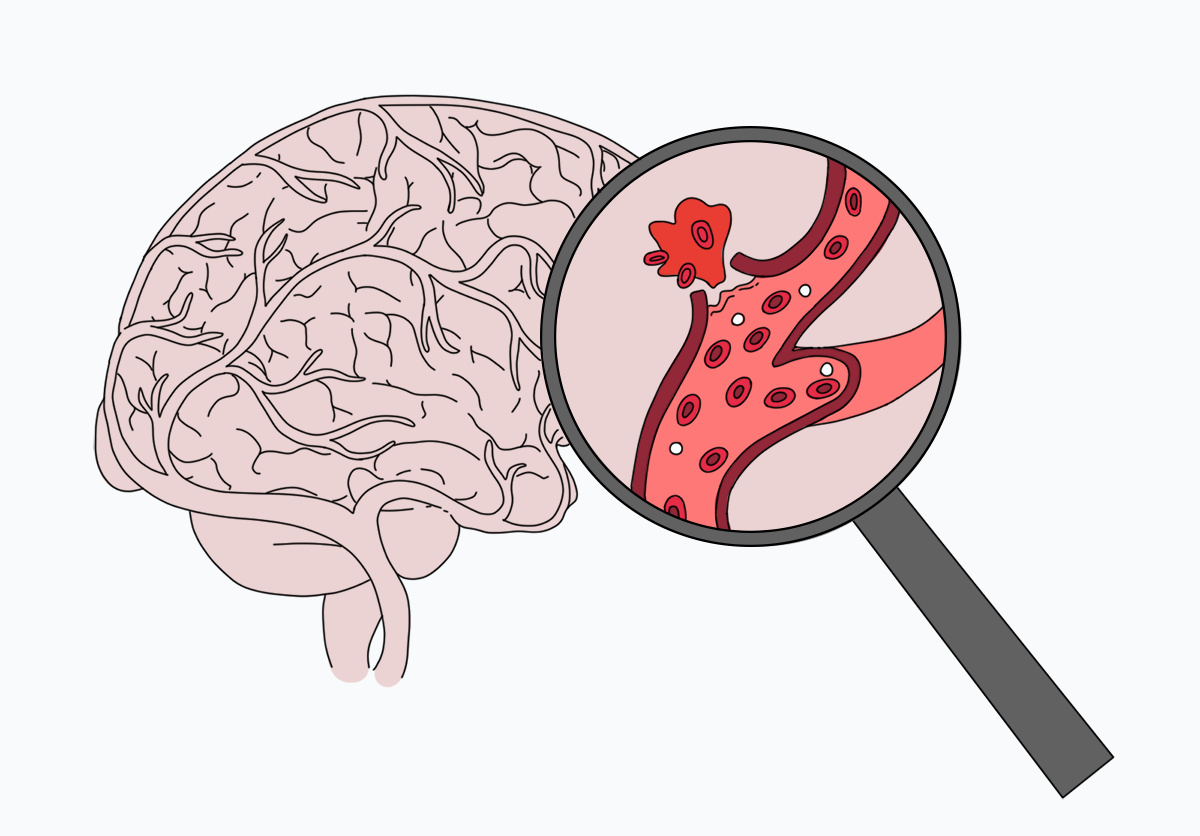

В широком смысле инсульт — это повреждение тканей мозга в результате нарушения кровообращения. По механизму воздействия его принято делить на два типа: ишемический, при котором клетки мозга недополучают крови и отмирают, и геморрагический, когда крови, наоборот, слишком много, она выходит из кровеносных сосудов и заливает часть мозга. В зависимости от места кровоизлияния геморрагический инсульт делят на внутримозговой и субарахноидальный; при последнем кровь попадает в пространство между оболочками мозга, в норме заполненное спинномозговой жидкостью.